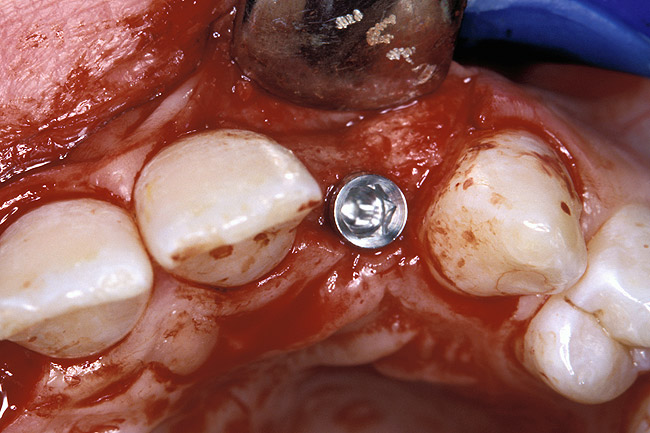

Before the day of surgery, the patient was seen by the orthodontist for the removal of the orthodontic brackets. The patient still was not pleased with the position of the two centrals, and it was determined that this would be addressed after implant placement (Figure 13A). The anatomical variations of the crestal tissue and lack of interdental papilla can be appreciated in the close-up views of the right and left sites (Figure 13B and 13C). There were no surprises on the day of surgery as all of the decisions were made during the planning phase, before the scalpel ever touched the patient. The occlusal view of the CT 3D model revealed the wider alveolar ridge on the right side and thinner crest on the left side (Figure 14A). This was confirmed when the full thickness mucoperiosteal flaps were elevated, and the underyling bone revealed (Figure 14B). The tooth-borne templates were designed to facilitate the drills and drilling sequence specific to the diameters of the predetermined implants (Figure 15A). Each template contained an embedded 5-mm long stainless steel tube, which was approximately 0.2-mm wider than each drill (just wide enough to allow for the drills to rotate freely). Once positioned over the natural teeth, the template was secure and offered precision accuracy in transferring the implant locations from the original software-designed plan, allowing the potential for internal and external irrigation (Figure 15B). The 3.7-mm diameter Tapered Screw-Vent implant drilling sequence requires three drills: pilot, intermediate, and final sizing. Thus, three separate templates were fabricated to a.commodate these sizes. The templates were removed easily and replaced with the next sequential size in less time than it takes to change the drill on the surgical handpiece. After the osteotomies had been.completed, the implants were delivered to the site (Figure 16A and Figure 16B). For this internal hex connection implant, the author r.commends that the flat of the antirotational hex be positioned to the facial for proper orientation of the restorative.components (Figure 17A). Preprepared margins were created from a milled titanium fixture mount transfer post, which was delivered to the implant as support for an immediate transitional restoration. The facial “dot” helped confirm the orientation of the abutment to the facially positioned flat side of the internal hex connection (Figure 17B). Before cementation of the transitional acrylic restorations, a closed-tray, fixture-level impression was made, and a soft-tissue model fabricated.

Figure 17a  By predetermining the necessary orientation of the restorative components, the implant’s antirotational hex was positioned correctly.

Figure 17a

Figure 17b  By predetermining the necessary orientation of the restorative components, the implant’s antirotational hex was positioned correctly.

Figure 17b